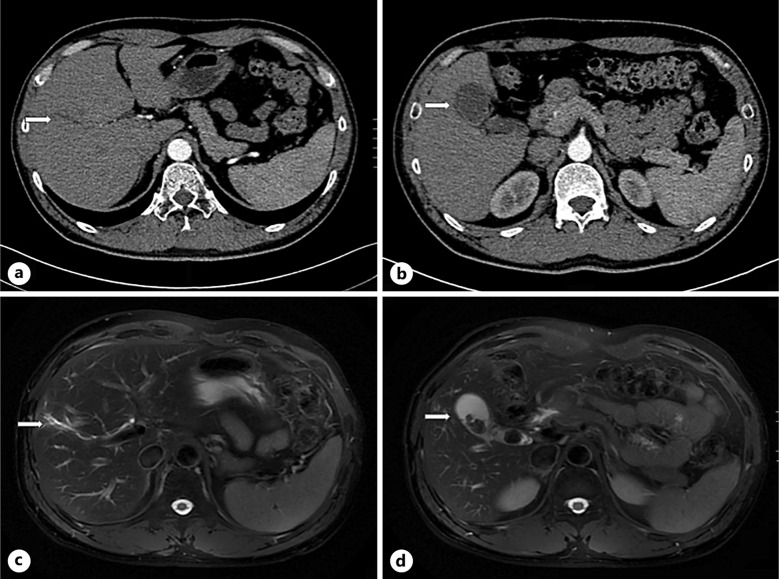

Case presentation: Seven aviation pilots who underwent laparoscopic cholecystectomy in recent 5 years were reviewed, and 3 cases who developed long-term PCS because of variations of bile duct were presented. Variations of bile duct included existence of accessory extrahepatic bile, absence of common bile duct, and absence of cystic duct. Long-term PCS was characterized as epigastric dull pain and diarrhea or sparse stool, and became aggravated when resuming trainings of flight stimulations. Dietary adjustment and oral antispasmodic or cholagogic drug therapy, combined with relieving apprehensions after surgery, helped them recover well and resume flight.